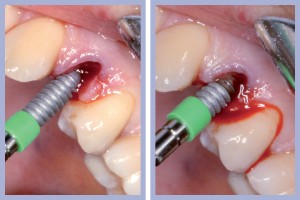

- Figg. 9a, b – Preparazione del sito di destra

- Figg. 10a, b – Preparazione del sito di sinistra

– Preparazione del sito implantare con tecnica flapless (Figg. 9-10);

Dopo l’estrazione, eseguita con i consueti passaggi di scollamento-lussazione-estrazione, la revisione chirurgica tramite cucchiaio alveolare consentiva la completa rimozione dei frustoli di tessuto di granulazione e di legamento parodontale residuo. La preparazione del sito implantare veniva effettuata con approccio flapless, ovvero senza l’esecuzione del lembo.

Una volta determinato, sul versante palatale dell’alveolo, il giusto asse di preparazione, si lavorava fino alla profondità programmata; la sequenza di frese comunemente impiegate per il diametro implantare da posizionare completava la preparazione dell’alveolo chirurgico. Non era richiesto l’uso della fresa svasatrice dal momento che a livello cervicale l’alveolo presentava un diametro maggiore di quello implantare.